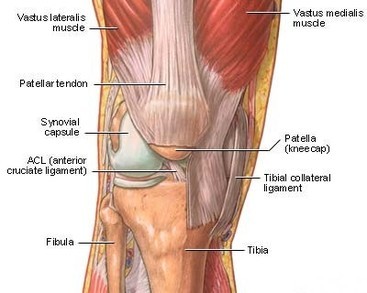

軟骨のすり減り、骨棘ができたり、半月板の変形、靭帯の緩み、膝のお皿の下にある脂肪の組織が変形する、筋力低下などの原因で膝の痛みを発します。